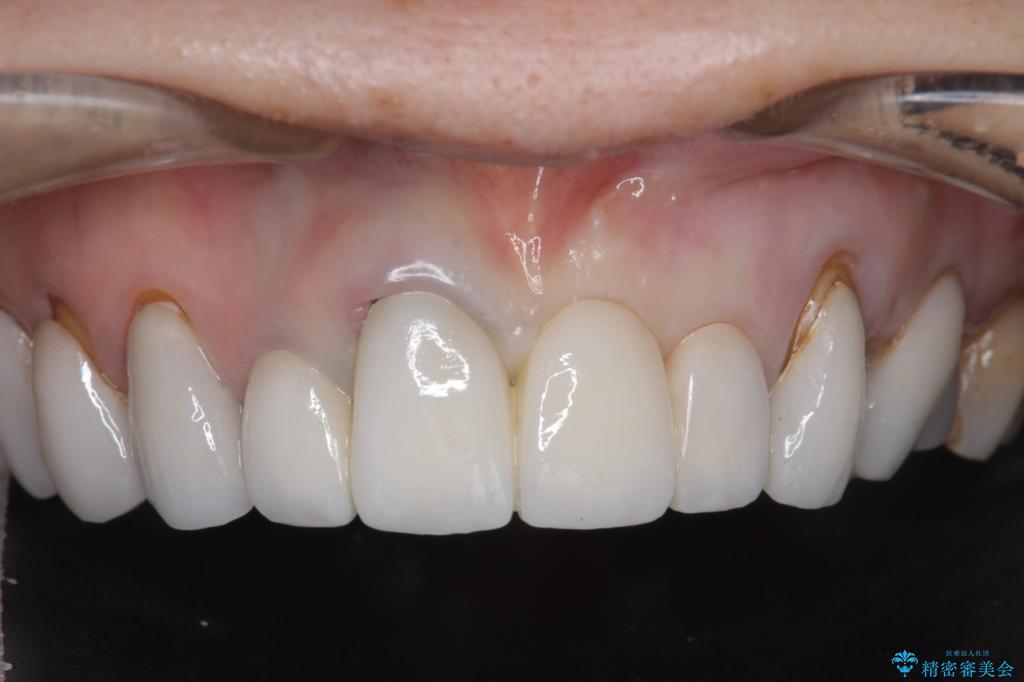

[ セラミック治療 ] 歯ぐきの際の黒ずみを改善したい

- 歯ぐきとセラミックの間の黒ずみが目立つので、きれいに治してほしい。と希望され来院されました。

歯ぐきの位置が変化しクラウン下の歯が見えるようになってしまったことで、審美障害が生じている状態です。

クラウンマージンの再設定を行うことで、黒ずんだ部分を再度覆い、審美障害を改善します。